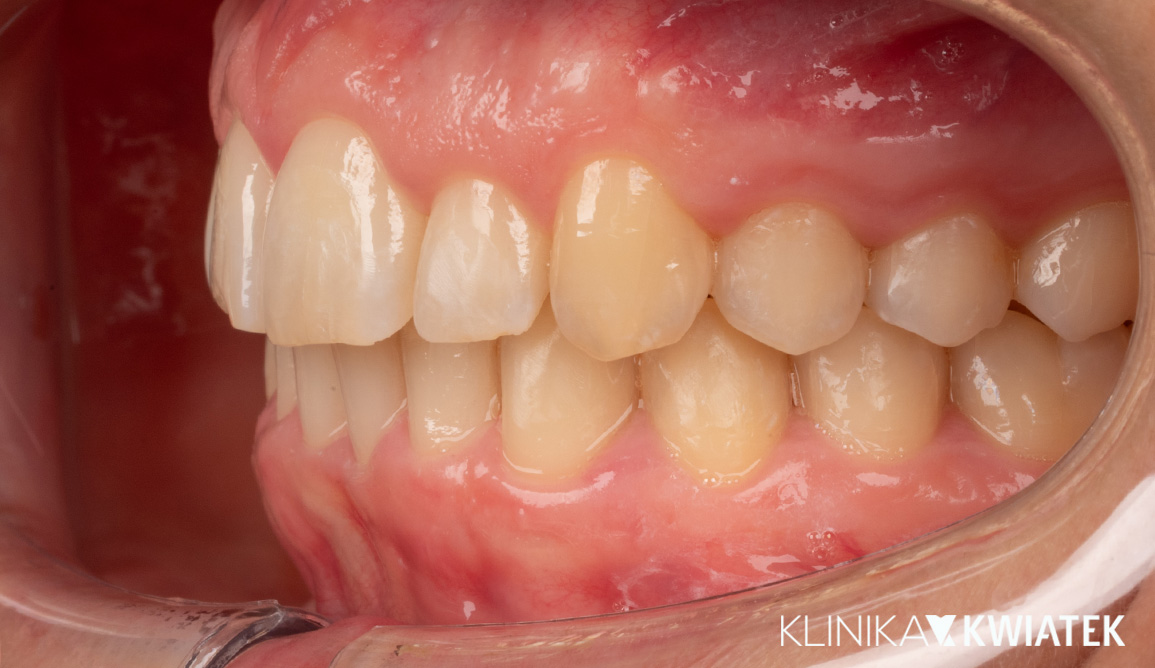

Kompleksowe leczenie i odbudowa funkcji – droga do pięknego uśmiechu

Do naszej Kliniki zgłosił się Pacjent z poważnymi problemami stomatologicznymi – licznymi ubytkami, nieprawidłowym zgryzem oraz widocznym starciem zębów, co wpływało na estetykę i funkcję. Przeprowadziliśmy kompleksowy plan leczenia: od diagnostyki, higienizacji i leczenia zachowawczego, przez szynoterapię i leczenie implantologiczne, aż po pełną odbudowę protetyczną. Efekt końcowy to zdrowy, harmonijny uśmiech oraz pełny komfort w codziennym funkcjonowaniu.